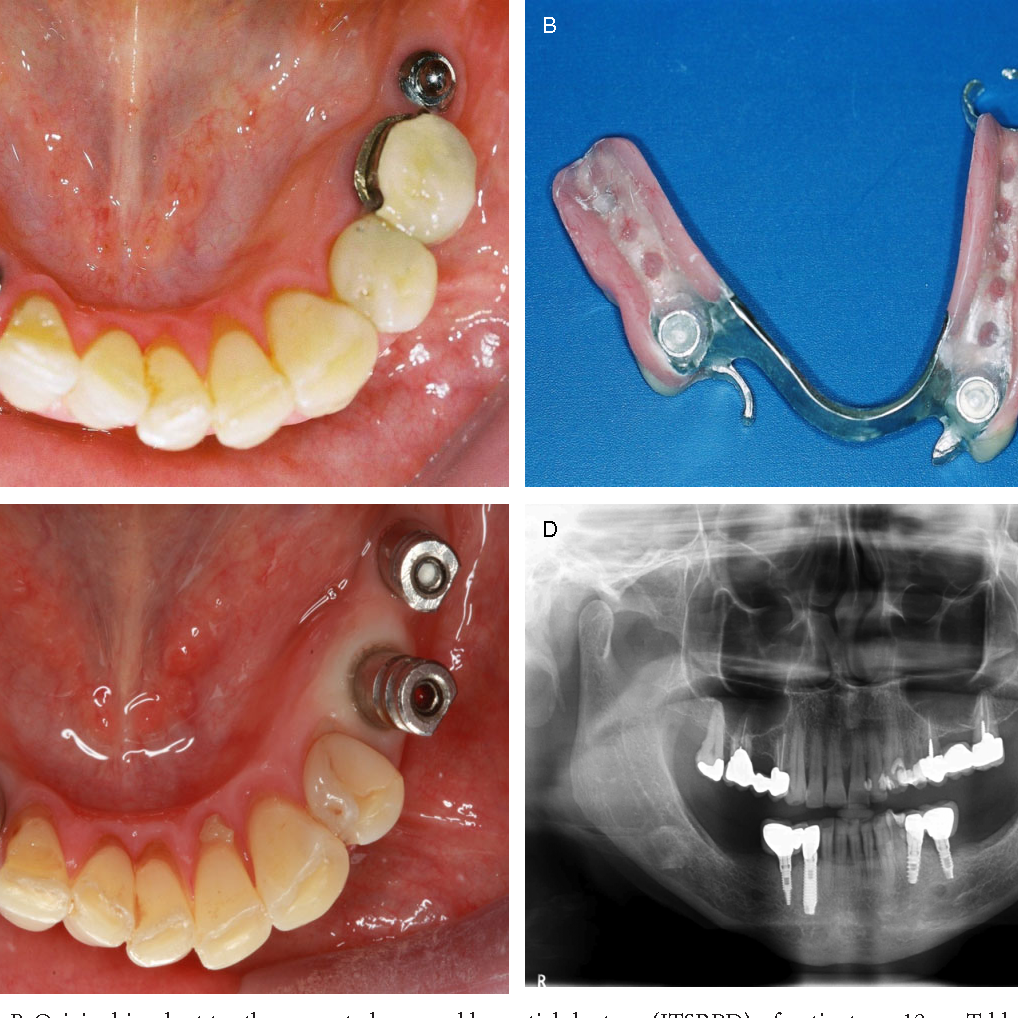

Implant-supported removable partial dentures (RPDs) combine

the benefits of dental implants with the flexibility of partial

dentures. This hybrid solution is especially suitable for patients

who have lost multiple teeth but not all teeth in an arch. The

implants provide stability and prevent bone resorption, while

the removable nature of the denture offers ease of cleaning

and maintenance. Here’s a general overview of the procedure

for placing implant-supported RPDs:

Implant-supported removable partial dentures (ISRPDs) represent a convergence of traditional removable prosthetics and contemporary implantology, orchestrating a symbiotic relationship that leverages the stability of implants while retaining the adaptability of a removable prosthesis. The structure essentially incorporates dental implants, usually integrated into the jawbone, which engage with specific attachments housed within the partial denture. This union not only confers enhanced stability and retention to the denture but also mitigates the classic limitations of conventional removable partial dentures, such as movement during function and potential tissue irritation. The functionality extends to improved masticatory efficiency, enriched aesthetic harmony, and enhanced prosthetic longevity, while still permitting the patient to remove the prosthesis for hygiene and maintenance.